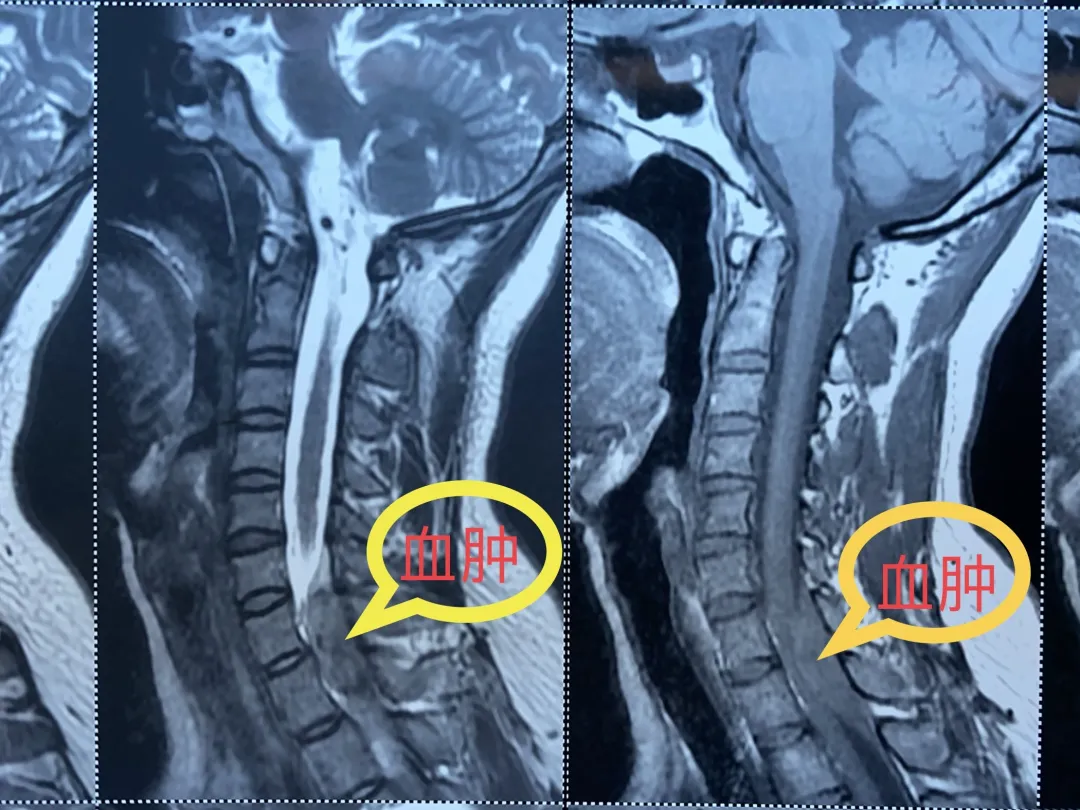

到医院后,急诊科医生迅速为小真做了各项检查,CT结果显示小真颈5/6椎间盘轻度中央型突出,医生为患者申请紧急核磁检查,结果显示:颈髓有一个巨大的肿物压迫着。

经神经外科医生判断,小真的情况是颈椎管内急性出血导致的,而不正确的扭动脖子和推拿按摩,很可能是导致她出现瘫痪的诱因。

她在做颈部的活动过程中很可能导致了颈部椎管内的出血,按摩推拿的过程造成了颈部的活动幅度更加变大,里面的出血很可能在这个基础之上有所增加。从片子我们可以看到,由于血肿的压迫使脊髓变得非常薄,病人的截瘫就是由于脊髓受压导致的。